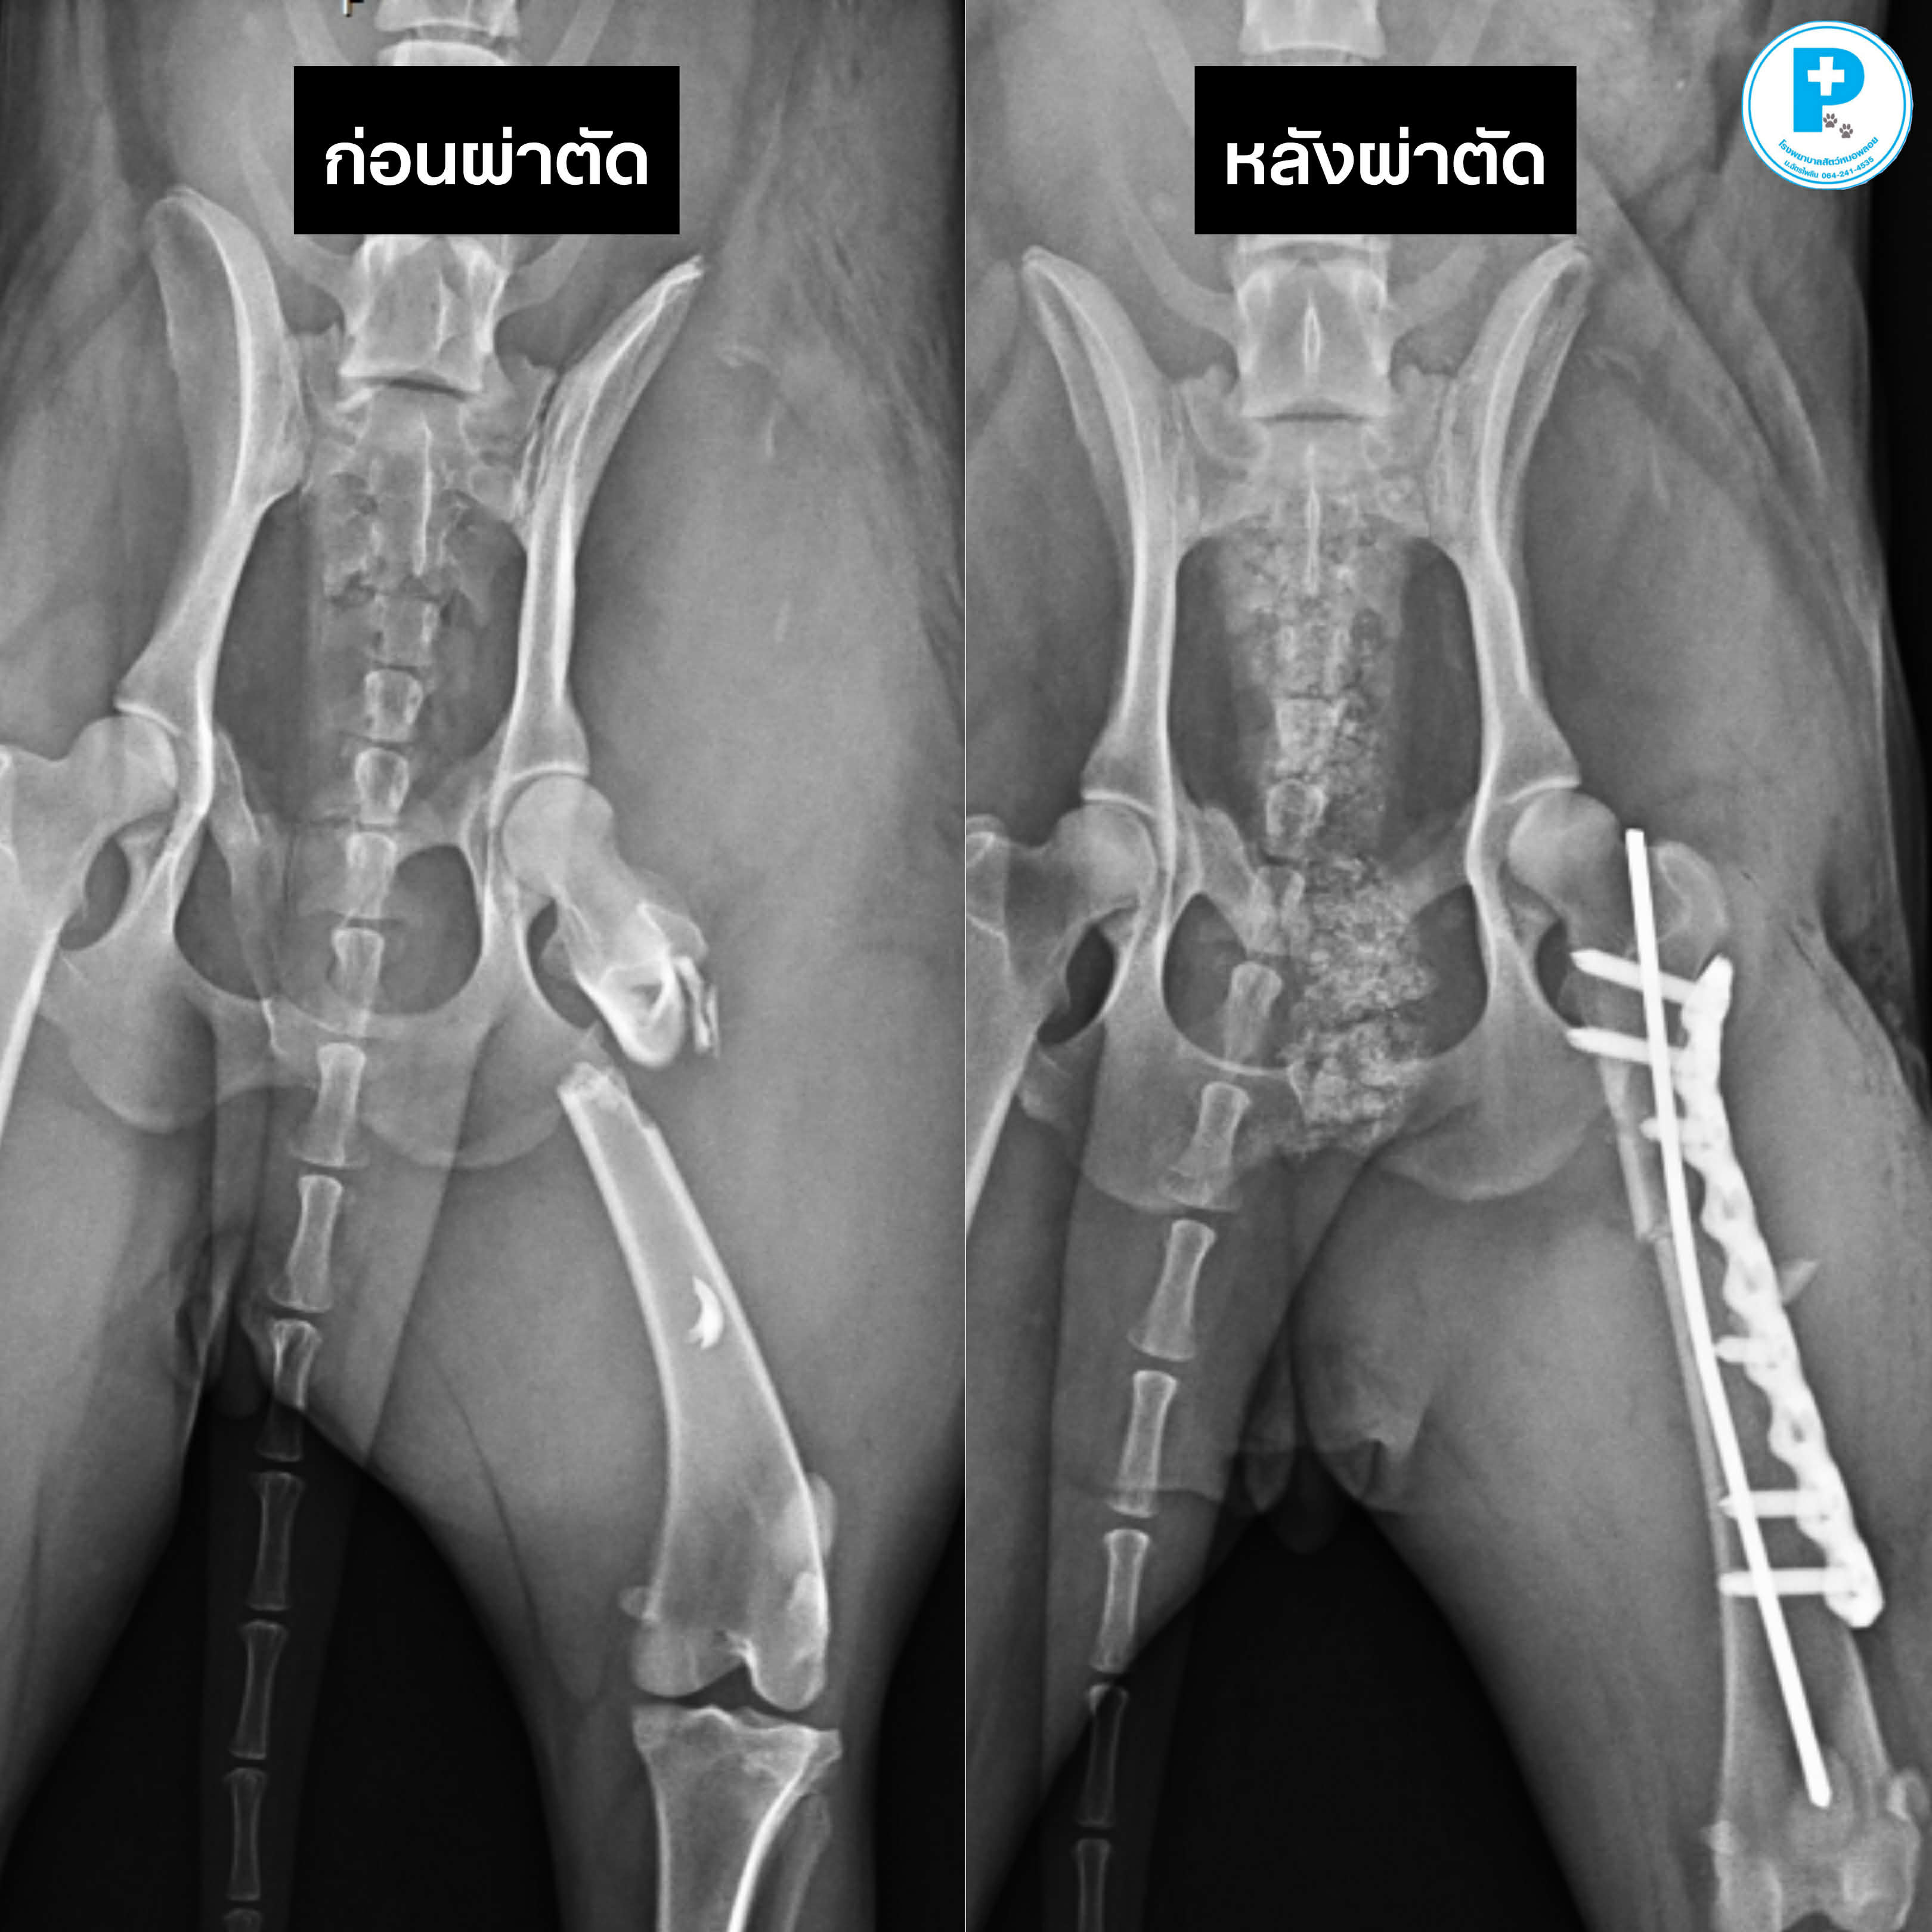

- น้องดำประสบอุบัติเหตุอย่างรุนแรง กระดูกเชิงกรานเคลื่อนทั้งสองข้าง (Both sacroiliac luxation) ร่วมกับภาวะไส้เลื่อนช่องท้อง (Abdominal herniation)

ก่อนผ่าตัด น้องดำมาที่รพส.ด้วยอาการ

• ขาหลังอ่อนแรง

• เจ็บเมื่อจับบริเวณเชิงกราน

• ผนังช่องท้องฉีกขาด ทำให้อวัยวะภายในเคลื่อนออกจากตำแหน่งปกติ

แนวทางการรักษา

ผ่าตัดจัดกระดูกด้วย Trans-iliac pin placement ร่วมกับ lag screw fixation

ซ่อมแซมผนังช่องท้อง (Abdominal hernia repair)การบาดเจ็บลักษณะนี้ หากปล่อยไว้อาจส่งผลต่อระบบประสาท การขับถ่าย และคุณภาพชีวิตระยะยาว

หลังผ่าตัด วางแผนทำกายภาพบำบัดเป็นลำดับ ควบคุมความเจ็บปวดอย่างใกล้ชิด ติดตามภาพรังสีประเมินการยึดติดของกระดูก

อุบัติเหตุอาจเกิดขึ้นได้เสมอ แต่การวินิจฉัยที่แม่นยำและการผ่าตัดที่เหมาะสม ช่วยให้เขากลับมายืนได้อีกครั้ง

ผ่าตัด: สพ.ญ.ณัฐฐ์ธวรรณ โสภิพันธ์ (หมอพลอย)

เรียบเรียง: น.สพ.นรภัทร โสภิพันธ์ (หมอพีท)